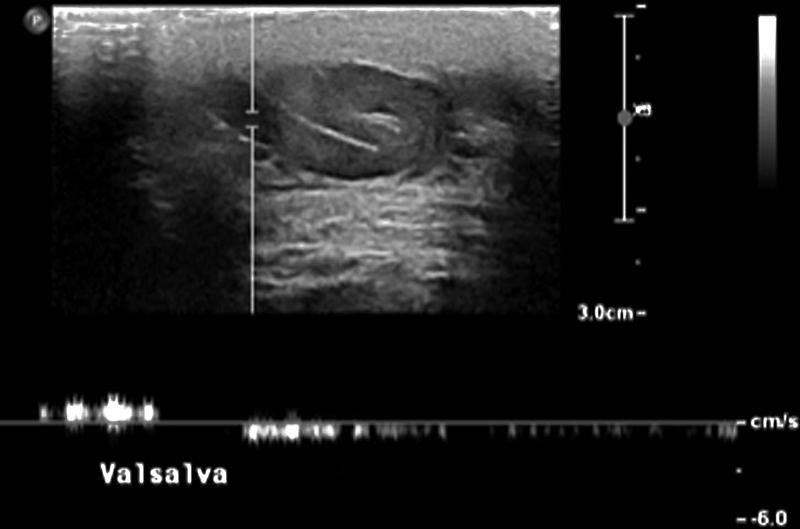

Manuver Valsalva (Tes Fungsional): Pada kedua posisi (terlentang dan berdiri), pasien harus diinstruksikan untuk melakukan manuver Valsalva (mengejan sambil menahan napas selama beberapa detik). Manuver ini secara dramatis meningkatkan tekanan intra-abdomen, yang diteruskan ke sistem vena. Pada individu dengan katup vena yang inkompeten, manuver ini akan memprovokasi atau memperburuk aliran darah retrograde (refluks), yang merupakan ciri khas hemodinamik dari varikokel. Manuver Valsalva mengubah pemeriksaan dari sekadar pengamatan anatomi menjadi tes fungsional yang dinamis untuk menilai kompetensi katup vena.

Gambar 2. Variciccel kiri, Gelombang USG doppler menunjukkan aliran balik dengan valsava

Spectral Doppler memberikan analisis kuantitatif yang lebih presisi. Dengan menempatkan gerbang sampel di dalam vena yang dicurigai, spektrum aliran dapat direkam. Refluks akan muncul sebagai gelombang aliran di bawah garis dasar (baseline). Parameter diagnostik utama di sini adalah durasi refluks. Menurut pedoman dari European Society of Urogenital Radiology (ESUR), refluks yang berlangsung lebih dari 2 detik selama manuver Valsalva dianggap patologis. Beberapa studi lain menggunakan ambang batas yang sedikit lebih rendah, yaitu >1 detik.